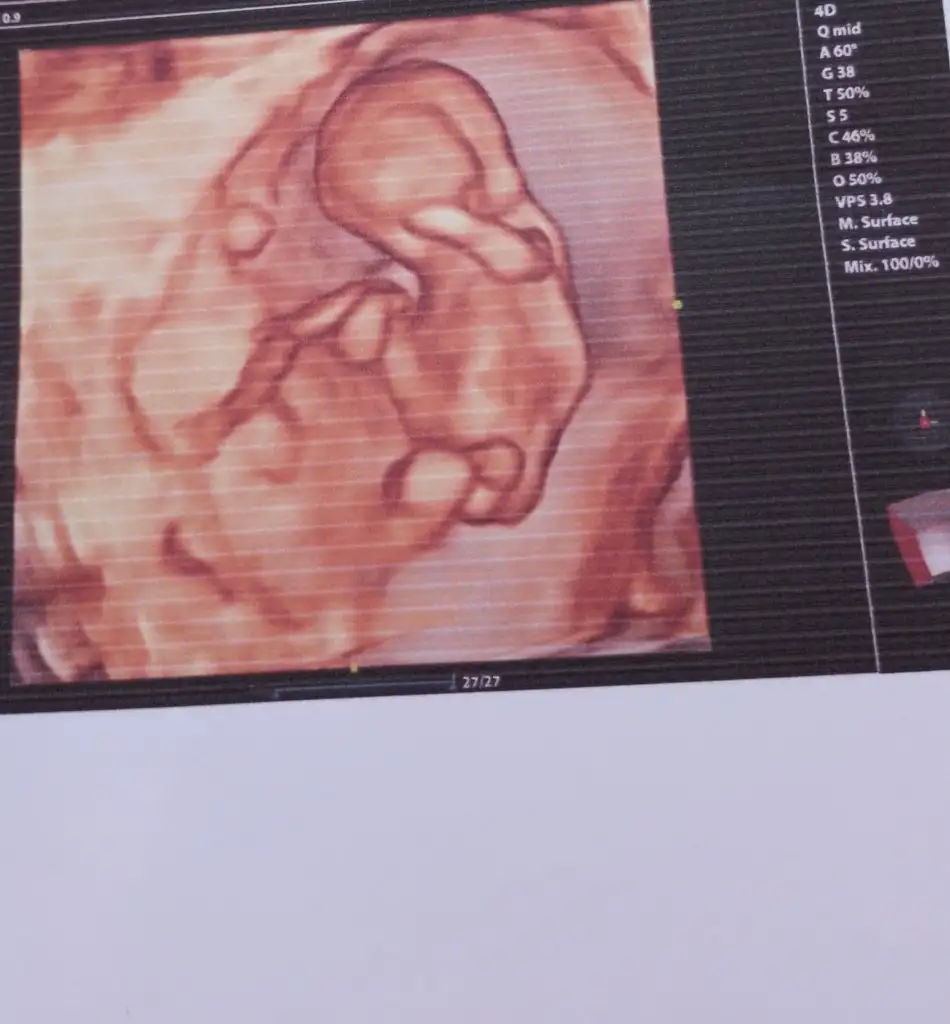

13+6 nubu kız gibi ama bacak arasında da çıkıntı var gibi sizin tahmininiz nedir

Eklentiler

• Screenshot_2023-11-21-20-22-33-531_com.miui.gallery.webp

17,7 KB · Görüntüleme: 126

• Screenshot_2023-11-21-20-21-29-746_com.miui.gallery.webp

19 KB · Görüntüleme: 116

• Screenshot_2023-11-21-20-20-53-023_com.miui.gallery.webp

18,8 KB · Görüntüleme: 105